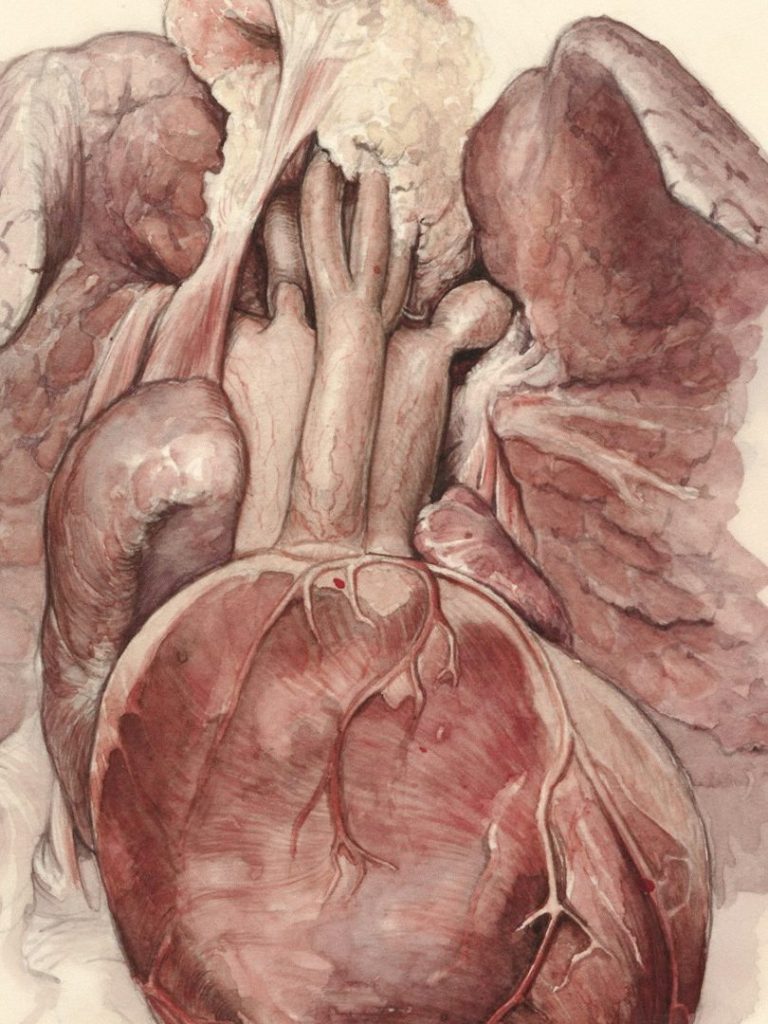

Das wahrhaftige und wirkliche Wissen über die 5 Herzkammer nach Yamsaro®/Natara®

Modul 1

Die göttliche Matrix in der 5 Herzkammer. Der Sitz der Keimblätter und der Seele.

Die 5 Herzkammer befindet sich direkt an der Hinterwand des Herzens.